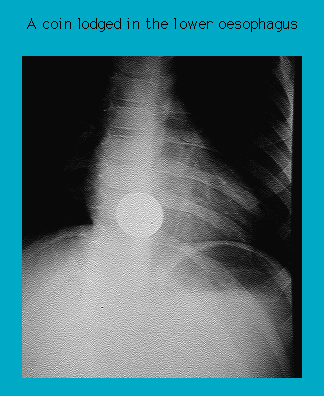

Radiograph of coin in the lower oesophagus